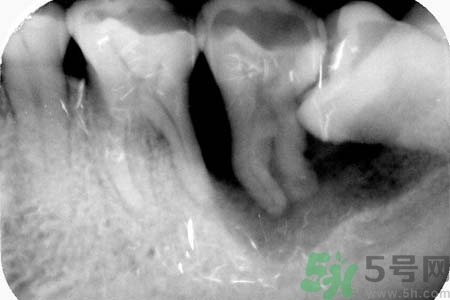

5、如果智齒經(jīng)常疼,而且疼的比較厲害,可能已經(jīng)引發(fā)牙冠周軟組織發(fā)炎,所以導(dǎo)致智齒腫脹、疼痛;再如果智齒長的位置很歪,影響其它牙齒正常咀嚼,也影響美觀,最好是考慮拔牙。拔牙前提是確保牙冠周圍沒有炎癥,才能安排拔牙,免除后顧之憂,拔智齒是拔牙里最難的一種,所以一定要到正規(guī)口腔醫(yī)院,請正規(guī)醫(yī)師進(jìn)行專業(yè)拔牙。

6、如果智齒經(jīng)常疼,而且疼的比較厲害,可能已經(jīng)引發(fā)牙冠周軟組織發(fā)炎,所以導(dǎo)致智齒腫脹、疼痛;再如果智齒長的位置很歪,影響其它牙齒正常咀嚼,也影響美觀,最好是考慮拔牙。拔牙前提是確保牙冠周圍沒有炎癥,才能安排拔牙,免除后顧之憂,拔智齒是拔牙里最難的一種,所以一定要到正規(guī)口腔醫(yī)院,請正規(guī)醫(yī)師進(jìn)行專業(yè)拔牙。